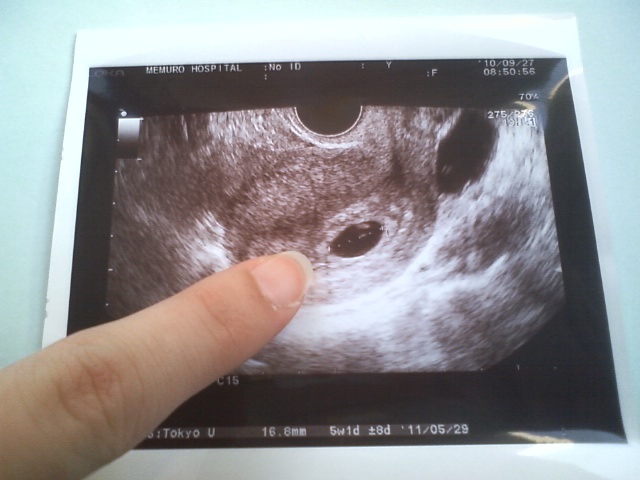

前回は初めての妊娠でお医者さんに 【子宮外妊娠かもしれない】といわれ とっても不安でみなさんに励ましのお言葉をたくさんいただきとっても励まされました泣き顔 このたび検診でやっと 【正常妊娠・心拍】が確認できました泣き顔 本当に本当に信じていて良かったです泣き顔 結婚5年目、正直会話のない時期もありました。 でも一年前処分されかけたわんこを譲り受け、わんこが妊娠発覚・帝王切開・人口保育を経てそだてたわんこたちを通して私たち夫婦には本当の子供のようでした。 それがあり二人の生活も会話がありわんたちがいて。本当に